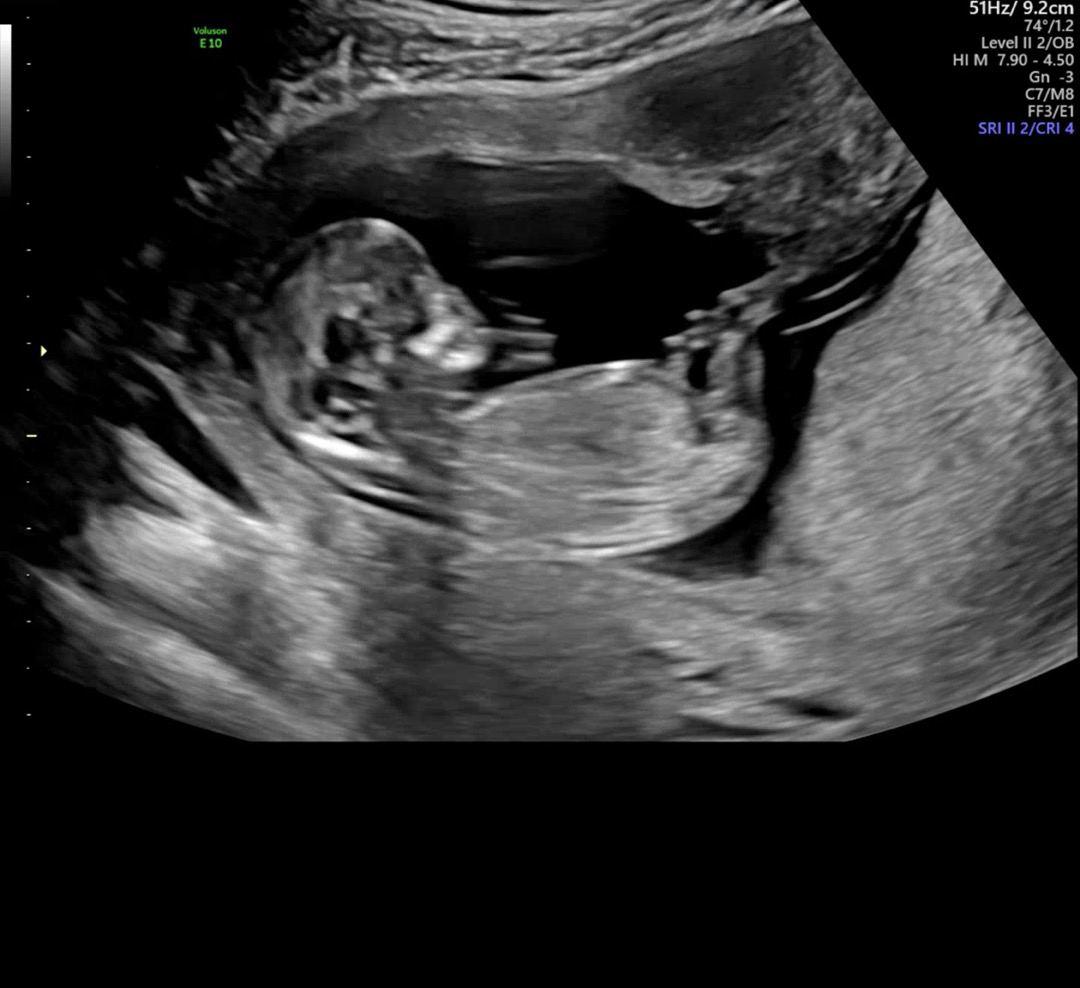

12주차 각도법 한번만 봐주세요><

12주차 각도법 한번만 봐주세요 봐도봐도 모르겠어용ㅠㅠ